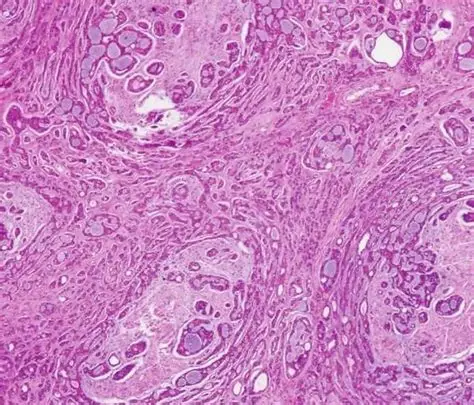

腺样囊性癌(Adenoid Cystic Carcinoma, ACC)最常见于唾液腺,但也可发生于气管、乳腺及泪腺,其最大特点在于生长缓慢但极易发生神经侵犯和远处转移(尤其肺转移),这使得传统“手术+放疗”的治疗模式在长期控制上面临挑战。

研究发现,约60%-80%的ACC患者存在MYB或MYBL1基因重排(Nature Reviews Cancer, 2022),这为靶向治疗提供了方向。美国多家癌症中心正在探索多靶点酪氨酸激酶抑制剂(TKI)的应用。